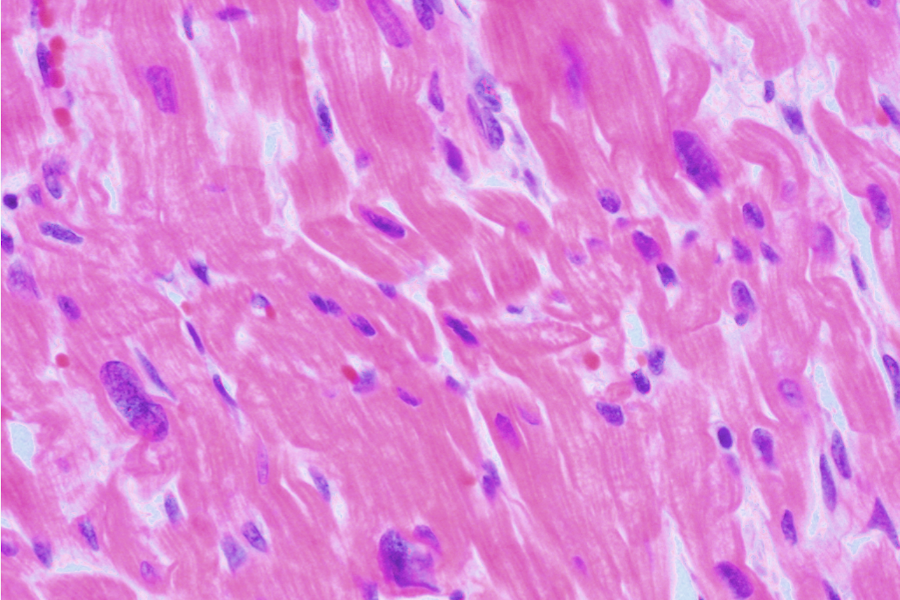

histologische Bilder

adultes Myokard

adultes Myokard

HFpEF = komplexes Krankheitsbild

- umfasst breites Spektrum unterschiedlicher Ätiologien

- Ausmaß wird durch Störung der Feinstruktur des Herzens erklärt